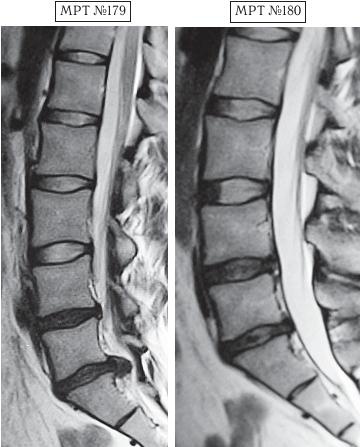

На МРТ № 179 наблюдается состояние поясничного отдела позвоночника (до лечения): сглаженность поясничного лордоза, протрузия (компенсированная спондилёзом) в сегменте LIV—LV, секвестрированная грыжа межпозвонкового диска в сегменте LV—SI, абсолютный стеноз позвоночного канала. На МРТ № 180 — состояние поясничного отдела позвоночника после лечения методом вертеброревитологии: естественный физиологический лордоз поясничного отдела позвоночника, отсутствие секвестрированной грыжи межпозвонкового диска в сегменте LV—SI, отсутствие стеноза. Но самое интересное можно рассмотреть на МРТ № 181 и МРТ № 182. ![]() На увеличенных фрагментах вышеприведенных снимков наблюдается состояние сегмента LV—SI до лечения (МРТ № 181) и после лечения методом вертеброревитологии (МРТ № 182). На МРТ № 182 чётко прослеживается не только отсутствие секвестрированной грыжи межпозвонкового диска в сегменте LV—SI но и активный процесс восстановления межпозвонковых дисков (репаративная регенерация) в сегментах LIV—LV, LV—SI, и главное — процесс восстановления их пульпозных ядер. Так что можно образно сказать, что данный парень вытянул в жизни, не без помощи своих родителей, счастливый билет: он уже практически здоров, грыжа диска устранена без операции и биомеханика позвоночника восстановлена, а для молодого организма это немаловажный фактор. Но главное, он получил бесценный, собственный опыт того, что компьютер компьютером, а собственное здоровье ценнее всего и его надо беречь смолоду. А вот второго парня вместе с его родителями я увидел только через полтора года после нашей первой встречи, когда они вновь пришли ко мне на консультацию в клинику. На этот раз состояние его позвоночника было удручающим. Оказывается, по инициативе родителей их семья посетила широко рекламируемую частную клинику, которая специализируется на кинезитерапии — лечение движением заболеваний позвоночника. Там с ними обстоятельно побеседовали по поводу того, как «активная кинезитерапия оказывает саногенетическое действие, устраняя патобиомеханический субстрат синдрома», что для людей, неискушённых в медицинских терминах, равносильно пафосной речи из советской комедии «Операция «Ы» и другие приключения Шурика»: «В то время, когда наши корабли бороздят просторы Вселенной…». А потом, чтобы пациент-клиент ничего не перепутал, выдали специальную брошюрку, где были подробно расписаны советы вместе с физическими упражнениями, направленными на укрепление мышц спины, которые по рекомендации врачей данной клиники необходимо было выполнять для «лечения» остеохондроза. К сожалению, на тот момент родители этого юноши не были осведомлены о негативном влиянии подобных упражнений, направленных на укрепление мышечного корсета, на позвоночник, поражённый дегенеративно-дистрофическим процессом. А когда случилась беда и пошли необратимые процессы, было уже поздно что-либо предпринимать. Вот уж правду в народе говорят: «Здоровье не купишь — его разум дарит».